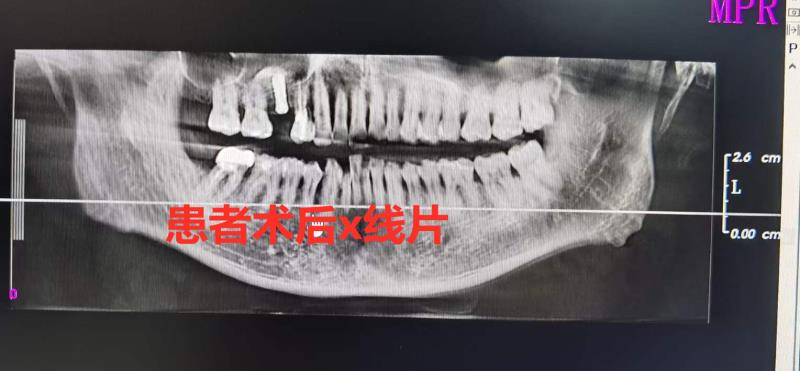

术后拍摄的口腔全景片显示,种植体周围的骨质宽度及高度合乎理想,手术圆满完成。